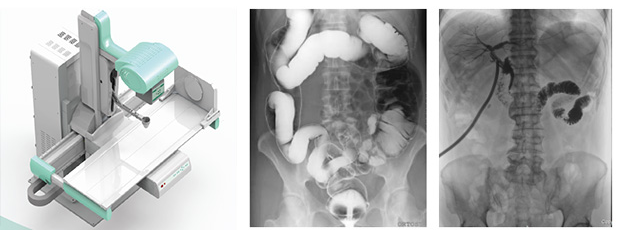

動(dòng)態(tài)DR是一種醫(yī)用X射線診斷設(shè)備的名稱,相比于普通DR的單一功能,動(dòng)態(tài)DR集合拍片、造影、胃腸、透視等多種功能,大幅提高診斷效率,避免漏診、誤診。擁有一臺(tái)動(dòng)態(tài)DR相當(dāng)于擁有整個(gè)放射科,能夠滿足普放科的常規(guī)拍片、胃腸造影、透視檢查等基本篩查功能需求。

動(dòng)態(tài)DR可以進(jìn)行實(shí)時(shí)造影劑追蹤、食道骨骼復(fù)位、輸卵管造影,實(shí)現(xiàn)全自動(dòng)攝影,通過透視消除常規(guī)DR的盲拍實(shí)現(xiàn)直接快速定位和精細(xì)診斷;具有豐富的數(shù)字化圖像處理軟件,性能良好,圖像分辨率高,能為醫(yī)生的臨床診斷提供了更優(yōu)異的影像數(shù)據(jù),提高診斷效率,大幅提高醫(yī)院工作效率。

普利德動(dòng)態(tài)DR臨床用途廣泛,一臺(tái)機(jī)器多種用途,可應(yīng)用于臨床各科室,如體檢科、內(nèi)科、外科、骨科、創(chuàng)傷科、急診科等。當(dāng)作為一臺(tái)普通DR X光機(jī)使用時(shí),能解決適用于全身各部位的數(shù)字化攝影,包括常規(guī)攝影(立位攝影、臥位攝影等,如胸片、頸椎、腰椎、腹部、頭顱、四肢等)和特殊攝影(傾斜攝影、角度攝影等,如瓦氏位、骶髂關(guān)節(jié)、髕骨軸位、跟骨軸位等);當(dāng)作為具有透視功能的胃腸機(jī)使用時(shí),能解決適用于全身各部位的數(shù)字化透視(如胸透、腹透等)、透視下定位、透視下穿刺及透視下數(shù)字點(diǎn)片攝影,還能解決適用于胃腸道造影檢查,如食管造影、上消化道造影、全消化道造影等,以及數(shù)字化造影檢查,如如口服膽囊造影、靜脈膽道造影、T管造影、逆行胰膽管造影(ERCP)、靜脈腎盂造影(IVP)、子宮輸卵管造影、脊髓造影等。